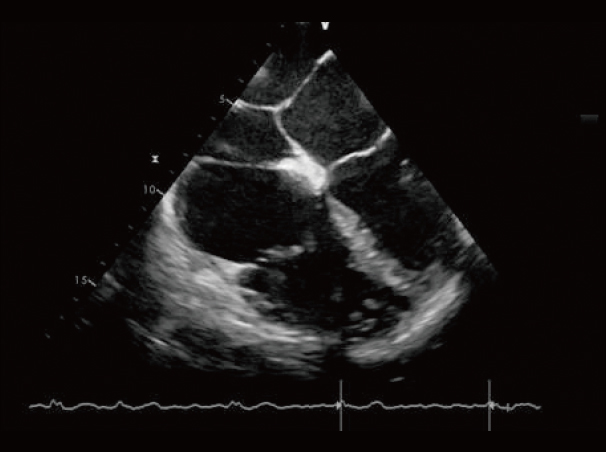

心脏,B/BC模式